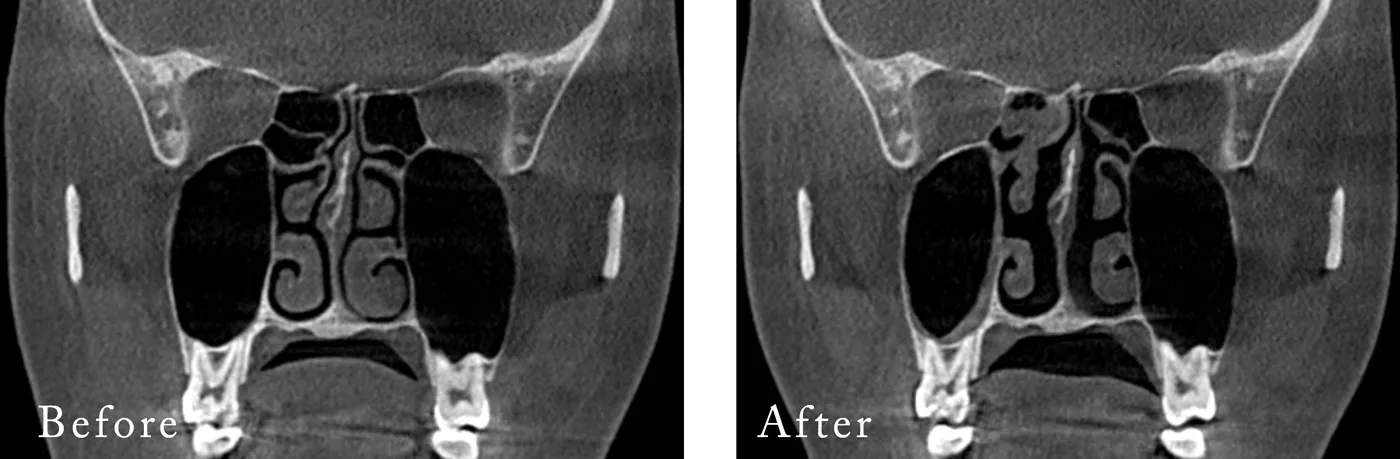

▼下鼻甲介縮小(鼻炎手術)を行った方のCT

標準的な費用 下鼻甲介縮小術(鼻炎手術)

単独¥330,000(税抜¥300,000)

他の手術と併用の場合¥220,000(税抜¥200,000)標準的な施術時間 15分 麻酔 全身麻酔¥220,000(税抜¥200,000)/

静脈麻酔¥110,000(税抜¥100,000)